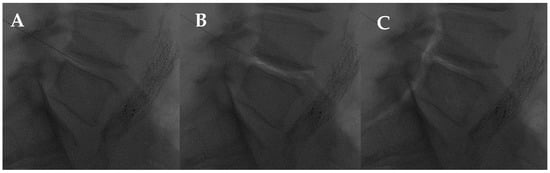

2.2.3. Facet Joint Approach

- Amoretti, N.; Amoretti, M.-E.; Hovorka, I.; Hauger, O.; Boileau, P.; Huwart, L. Percutaneous Facet Screw Fixation of Lumbar Spine with CT and Fluoroscopic Guidance: A Feasibility Study. Radiology 2013, 268, 548–555. [Google Scholar] [CrossRef]

- Lilius, G.; Laasonen, E.; Myllynen, P.; Harilainen, A.; Gronlund, G. Lumbar facet joint syndrome. A randomised clinical trial. J. Bone Jt. Surg. Br. 1989, 71-B, 681–684. [Google Scholar] [CrossRef]

- Carette, S.; Marcoux, S.; Truchon, R.; Grondin, C.; Gagnon, J.; Allard, Y.; Latulippe, M. A Controlled Trial of Corticosteroid Injections into Facet Joints for Chronic Low Back Pain. N. Engl. J. Med. 1991, 325, 1002–1007. [Google Scholar] [CrossRef] [PubMed]